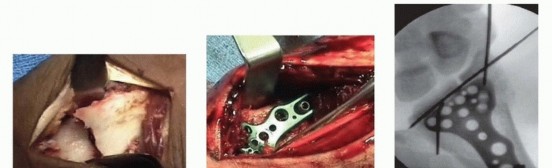

### TECH FIG 3 • A. The PA radiograph shows a displaced fracture of the radial styloid. B. This lateral radiograph shows metaphyseal comminution associated with the displaced radial styloid fragment. Because of the metaphyseal comminution, it was decided to stabilize the fracture using a volar plate.

* Open Reduction and Stabilization Perform a standard volar approach, and do not open the radiocarpal joint capsule ( TECH FIG 4A). The radial styloid fragment and the volar ulnar fragment are reduced to the shaft under direct visualization. The radial styloid fragment is provisionally pinned.*

### TECH FIG 4 • A. A standard volar approach is made, centered over the flexor carpi radialis tendon, and the fracture site is exposed. B. A volar distal radius locking plate is applied. The initial screw is placed through the proximal plate to secure the plate to the shaft. C. The intra-articular reduction is viewed under fluoroscopy and provisionally pinned. A displaced intra-articular fracture fragment can still be identified. D. The arthroscope is in the 3-4 portal, showing the volar capsule blocking reduction of the radial styloid fragment. E. Joysticks previously inserted into the radial styloid fragment are then used to control and anatomically reduce the radial styloid fragment. F. The arthroscope is in the 6R portal looking across the wrist. Anatomic reduction of the radial styloid fragment is documented. G. Once the anatomic restoration of the articular surface is evaluated both arthroscopically and fluoroscopically, the distal screws are placed in the plate. H. Fluoroscopic view showing anatomic restoration to the articular surface of the distal radius. I. The patient had an associated osteochondral fracture of the lunate, not visible on plain radiographs. The displaced fragment is arthroscopically removed.

Apply a volar distal radius locking plate to stabilize the volar bone fragments ( TECH FIG 4B). Place a screw in the proximal portion of the plate first to reduce the plate to the shaft. Provisionally pin the distal fragments through the plate. Manipulate the articular fragments under fluoroscopy to obtain as anatomic a reduction as possible ( TECH FIG 4C,D). Suspend the wrist in the traction tower and reduce the articular fragments arthroscopically ( TECH FIG 4E,F). If articular reduction is not anatomic, remove the pins and fine-tune the reduction. Once the fracture reduction is thought to be anatomic, place the distal screws through the plate ( TECH FIG 4G-I). It is important that the fracture be reduced to the plate, with no gap between the plate and the bone. This can be achieved by flexion of the wrist in the tower and by insertion of a nonlocking screw first, before the insertion of standard locking screws. Place the remaining proximal and distal screws if the reduction is anatomic under both fluoroscopy and arthroscopy. 1. ### Reduction and Stabilization of a Dorsal Die-Punch Fragment It is not possible to see the reduction of a dorsal die-punch fragment through the volar approach when stabilized with a plate. Arthroscopy can be helpful in this scenario. Insert the volar plate as previously described and provisionally fix the device to the radius. Frequently, the dorsal fragment may still be slightly proximal in relation to the radial shaft. The dorsal die-punch fragment is best seen with the arthroscope in the 6R portal. Establish the volar radial portal between the radioscaphocapitate ligament and the long radiolunate ligament, as viewed directly through the previous performed volar approach. 23 Percutaneously elevate and anatomically reduce the dorsal diepunch fragment as viewed arthroscopically. Once this has been achieved, place the screws into the plate and observe their path arthroscopically to ensure adequate stabilization of the dorsal die-punch fragment. 2. ## Ulnar Styloid Fractures Following anatomic reduction of the distal radius fracture, insert the arthroscope in the dorsal 3-4 portal and the probe in the 6R portal. Palpate the tension of the articular disc. Good tension indicates that the majority of the peripheral TFCC fibers are intact or still attached to the proximal ulna. A peripheral tear of the articular disc is repaired arthroscopically when detected. 30 Stabilization of a large ulnar styloid fragment is considered when the articular disc is lax by palpation and no peripheral TFCC tear is identified ( TECH FIG 5). In this instance, the majority of the fibers of the TFCC are attached to the displaced ulnar styloid fragment. Make a small incision between the extensor carpi ulnaris and the flexor carpi ulnaris tendons and identify the fracture site. Retrieve the distal fragment, which often displaces in a distal and radial direction. Mobilize the styloid fragment using a no. 15 blade, taking care to protect the TFCC insertion. Reduce the fragment anatomically, under direct visualization, and insert a guidewire in a retrograde manner for provisional stability. Stabilize the ulnar styloid fragment using either a tension band technique (with wire and two K-wires) or, preferably, using a micro headless cannulated screw. Place the cannulated headless screw over the guidewire and verify fracture reduction with fluoroscopy. Insert the arthroscope into the 3-4 portal and the probe into the 6R portal to document restoration of TFCC tension.